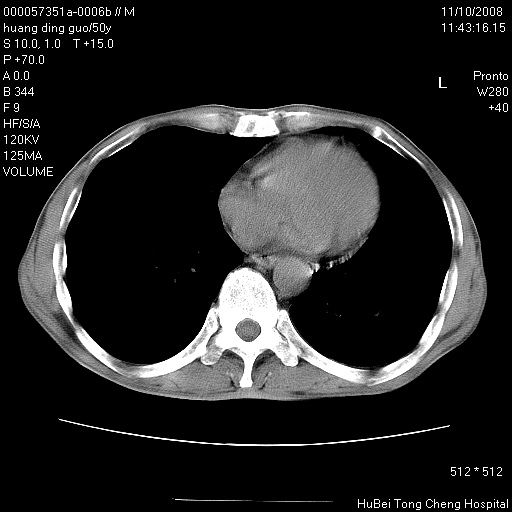

患者 男,50岁。左侧腰背部疼痛3月余,伴消瘦。平素健康,无传染病史。

胸部ct轴位平扫(层厚10mm,螺距1.5,重建间隔10mm),图像如下:

左肺下叶背段有一厚壁空洞,外壁呈锯齿状伴毛刺改变。空洞相邻胸膜有牵拉改变。左肺下叶血管支气管束不规则增粗,小叶间隔增厚。胸椎骨质破坏。考虑左肺下叶周围型肺癌伴左肺下叶癌性淋巴管炎、胸椎转移。

左肺下叶背段有一厚壁空洞,外壁呈锯齿状伴毛刺改变。空洞相邻胸膜有牵拉改变。左肺下叶血管支气管束不规则增粗,小叶间隔增厚。胸椎骨质破坏。考虑左肺下叶周围型肺癌伴阻塞性肺炎、胸椎转移。其他待排

左肺下叶背段有一厚壁空洞,内壁不规则,外壁呈锯齿状伴毛刺改变。空洞相邻胸膜有牵拉改变。周围呈絮状炎性改变,左肺下叶血管支气管束不规则增粗,小叶间隔增厚。胸椎骨质破坏。考虑左肺下叶周围型肺癌伴左肺下叶阻塞性肺炎、胸椎转移。